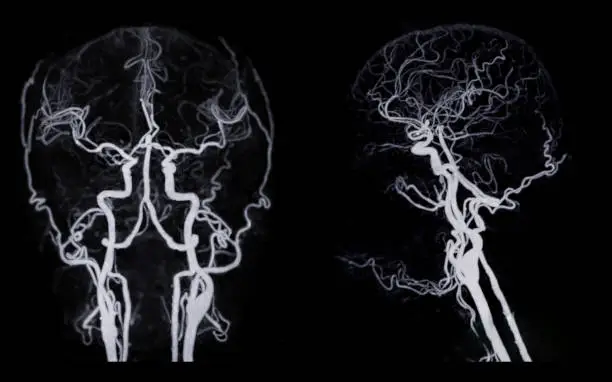

뇌혈관 조영술은 뇌혈관 상태를 정확히 진단하기 위해 시행되는 중요한 검사 중 하나입니다. 이 검사는 혈관의 구조를 확인하고 이상을 발견하는 데 매우 유용하며, 특히 뇌졸중, 뇌동맥류, 혈관 협착 등 중대한 질환을 진단하는 데 필수적입니다. 검사 자체는 다소 침습적이고 방사선과 조영제를 사용하므로 이에 따른 부작용 가능성도 존재하지만, 그 중요성 때문에 많은 환자들이 이 검사를 필요로 합니다. 이제 뇌혈관 조영술의 비용, 검사 절차, 부작용 및 보험 처리 등에 대해 자세히 알아보겠습니다.

뇌혈관 조영술은 고도로 전문적인 장비를 사용하여 혈관의 상태를 확인하는 검사입니다. 이 과정에서 카테터를 혈관에 삽입하고, 조영제를 주입한 후 X-ray를 통해 혈관을 촬영합니다. 일반적으로 팔이나 사타구니 부위에 카테터를 삽입하며, 혈관을 통해 뇌로 조영제를 전달합니다. 조영제가 혈관을 통과하면, 의료진은 혈관의 상태를 실시간으로 확인할 수 있습니다.